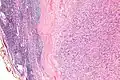

| Micrograph of an intranodal palisaded myofibroblastoma. H&E stain. | |

IPMs are diagnosed by examination of the tissue by a pathologist. They have a rim of peripheral lymphoid tissue (remnant of a lymph node) and consist of spindle cells with nuclear palisading. Red blood cell extravasation is common and blood vessels surrounded by collagen with (fine) peripheral spokes (amianthoid fibers) are usually seen.[2]

Immunostains for smooth muscle actin and cyclin D1 are characteristically positive. The main histologic differential diagnosis is schwannoma.

Low mag.